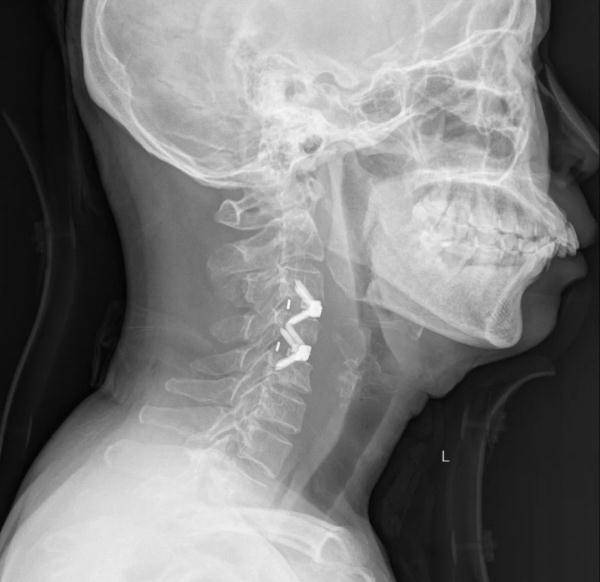

福建长乐漳港的王女士颈肩部反复疼痛 , 近日去医院就诊 , CT检查把所有人吓了一跳 。 她得的是“颈椎结核” , 而且C4、C5两节颈椎已经被“吃掉”近一半 , 有瘫痪的风险 。

在医院疼痛科 , 医生给王女士做了影像检查 , 发现她的颈椎周围形有大量脓肿 , C4、C5椎体的骨质已经被吞噬得“面目全非” ,出现了几处明显的缺口 。

如图 , 红圈部分↓↓↓

医生询问中发现 , 王女士的丈夫曾经患有肺结核 , 最终 , 经过医院多科专家会诊 , 确定王女士是“颈椎结核” , 立即对她实施了手术 。 术后 , 王女士感觉颈肩已经恢复正常 , 目前已经出院回家 。